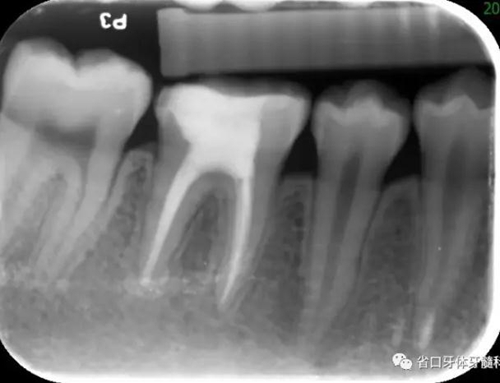

圖4 根管治療術(shù)后17個(gè)月:根分叉和根尖低密度影基本消失

2.本病例為牙髓組織來(lái)源引起齦緣、根分叉至根尖周區(qū)域貫通性的牙周組織損傷,在本病例的治療中,主要針對(duì)牙髓疾患行根管治療,牙周治療僅在初次治療時(shí)行牙周的簡(jiǎn)單處理,結(jié)果表明:完善的根管治療即獲得了良好的牙髓炎癥控制與牙周組織的愈合。